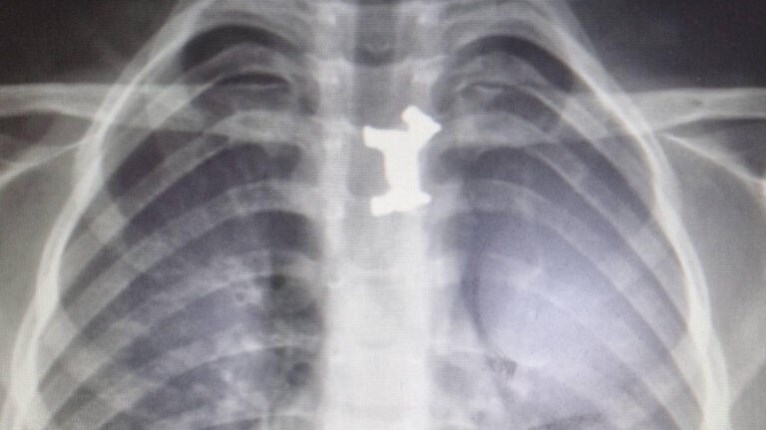

Το αγοράκι εμφάνισε σιελόρροια, οι γονείς του το πήγαν στο Γενικό Νοσοκομείο Σερρών όπου εξετάστηκε από τους γιατρούς, η ακτινογραφία έδειξε ότι είχε καταπιεί και είχε σφηνώσει στον οισοφάγο του ένα μεταλλικό παιχνίδι. Αποφασίστηκε η διακομιδή του στο Ιπποκράτειο Νοσοκομείο Θεσσαλονίκης.

Εκεί οι παιδίατροι ακολούθησαν την προβλεπόμενη διαδικασία σε αντίστοιχες περιπτώσεις, το πρωί υποβλήθηκε σε χειρουργική επέμβαση και οι γιατροί κατάφεραν να αφαιρέσουν με επιτυχία το μεταλλικό σκυλάκι από τον οισοφάγο του παιδιού.